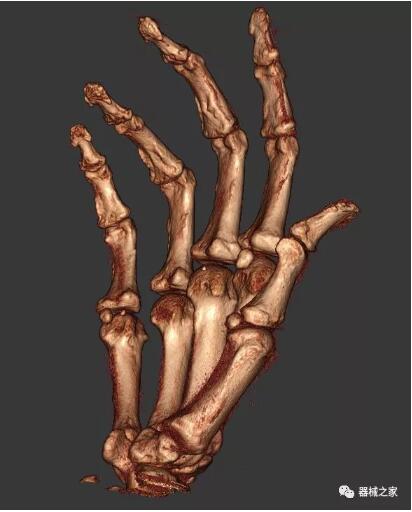

另外一款被稱為世界上最小的CT,它的重量?jī)H300磅,不僅能夠掃查足部,還可以檢查膝蓋和上肢等。

與上面介紹的CT一樣,它同樣具有輻射低、占地空間小(23*36)的特點(diǎn),隨開(kāi)隨用(支持直接接入墻上的插座)。

這款CT使用非常方便,通過(guò)上下移動(dòng)保持與患者的手臂或者雙腿齊平,掃描快速,僅需要30秒左右就可以完成掃查。

以上介紹的CT均來(lái)自國(guó)外同一家公司,這些CT均配置了可視化軟件,可以進(jìn)行切片、3D重建以及大型CT附帶的所有典型的操作功能。

以下是這些“特立獨(dú)行”的CT所拍出來(lái)的圖像: